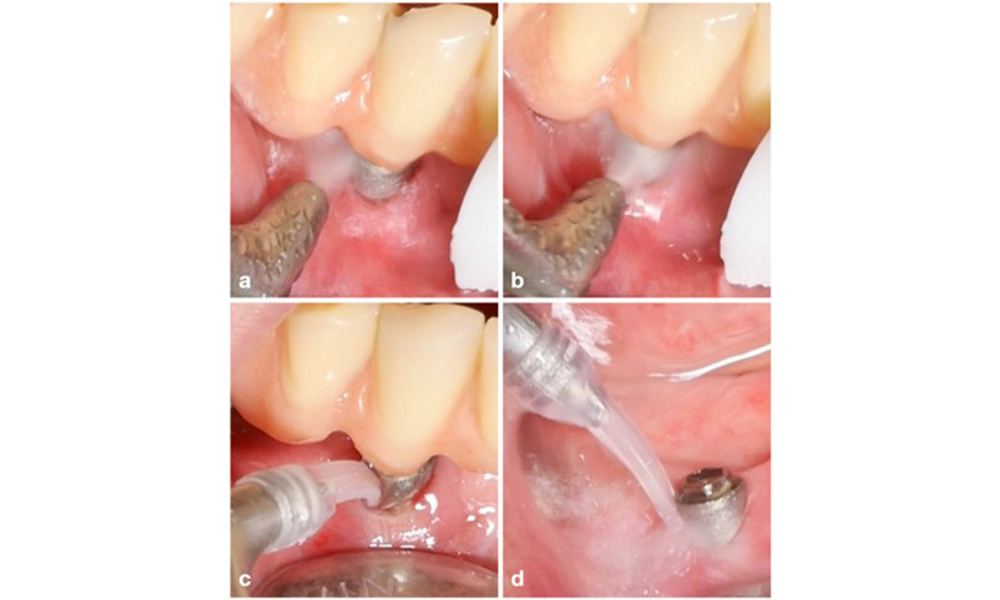

Defect extent, implant position, and its strategic importance determine whether an implant can or should be treated. Similar to a non-treatable (hopeless) implant, a severely affected implant in a multiple-unit restoration may be irrelevant for treatment, as its loss does not compromise the prosthetic restoration. Consequently, it is advisable to consider explantation either upon diagnosis or during surgical intervention (figure 8).

The prosthetic restoration should be removed during both non-surgical and surgical treatment to improve access to the implant surface. The choice of surgical intervention (e.g., resective, reconstructive, or combined) depends on several factors: (1) defect morphology (e.g., horizontal, dehiscence, intra-osseous, or combined) (figure 10), (2) implant surface (i.e., turned or modified/”rough”), and (3) presence or absence of sufficient keratinised and attached mucosa.